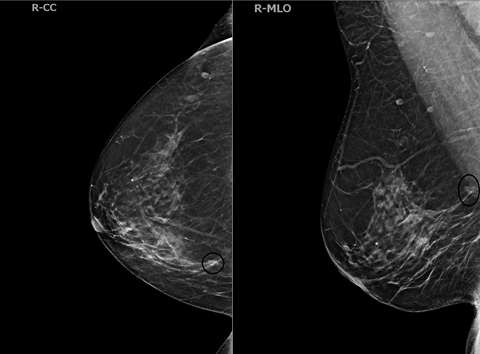

Case: Invasive Lobular Carcinoma Figure 4

Screening DBT on a 75-year-old female revealed an asymmetry in the central region of the right breast at posterior depth located 10 centimeters from the nipple. There is a probable correlate on medial breast on CC view.